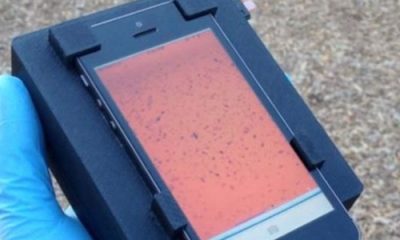

Especialistas em bioengenharia desenvolveram um sistema que permite que smartphones sejam usados para detectar a presença de parasitas no sangue. O sistema, chamado CellScope, permite que...